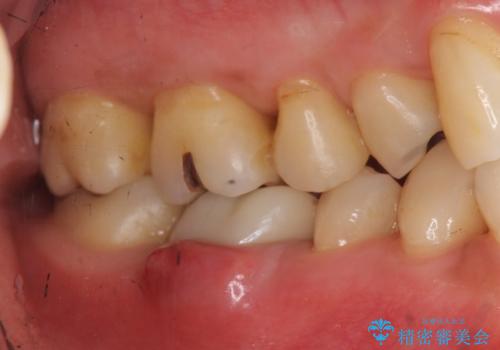

初診時には歯肉が腫れており、膿が出ている状態でした。

また、根の詰め物が根尖孔外(根の先の外の骨の部分)に盛大に漏れ出しており、歯周ポケットと根尖病巣が交通しているような状態でした。

初めての根の治療には見えないくらい、かなり歯が削ってあり、薄くなっていて割れても仕方ない状態でした。前の状態を見ていないので何とも言い難いですが、他の歯に比べこの歯だけ極端に状態が悪かったです。